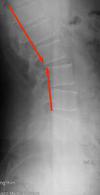

And finally, I must add that due to a sport injury which incurred when I was about 14 years old, I twisted my left foot. As a result my left foot is almost flat and perhaps my left leg is a bit shorter. I never addressed that injury. So my feet are not symmetrical now. This could explain the abnormal curve you see in the x-ray from my spine. I can provide much more details but allow me to await your response first.

Let's start with the x-rays. There are three significant findings. Firstly on the lateral lumbar (is an extension view?) there a sharp posterior angulation of L2 on L3 which is indeed where the superior cluneal nerves emanate from.